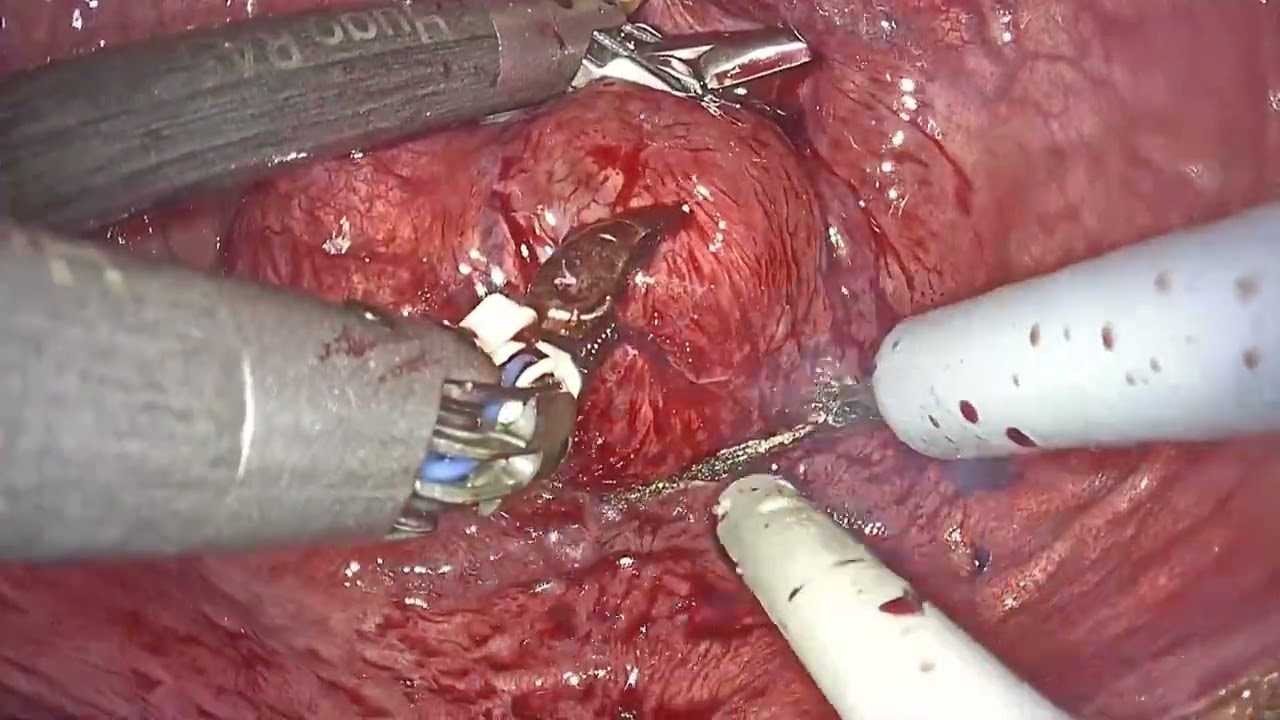

Jaipur Saturday Session 7 IVC Thrombus

#360 Robotic Assisted Right Adrenalectomy with IVC thrombectomy Dr. Deepak Kaddu

Complete minimally-invasive surgery for level IV Renal Cancer

A Step-Step Approach to Robotic Assisted Level 2 IVC Thrombus

KS Awards, Robotics ';